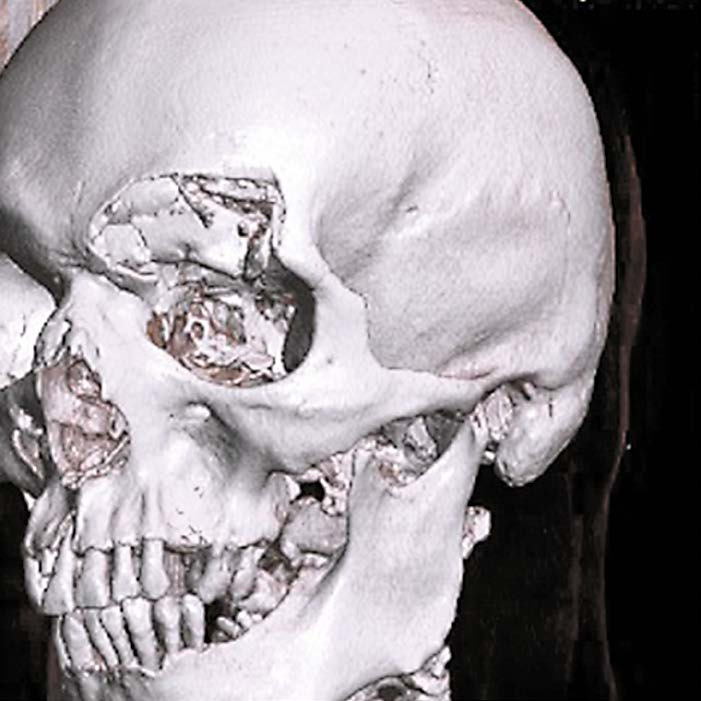

На снимке по МСКТ костей черепа в 3D-реконструкции определяется депрессионный вдавленный многооскольчатый перелом лобной пазухи, левой орбитальной пластинки.

На снимке по МСКТ костей черепа в 3D-реконструкции определяется депрессионный вдавленный многооскольчатый перелом лобной пазухи